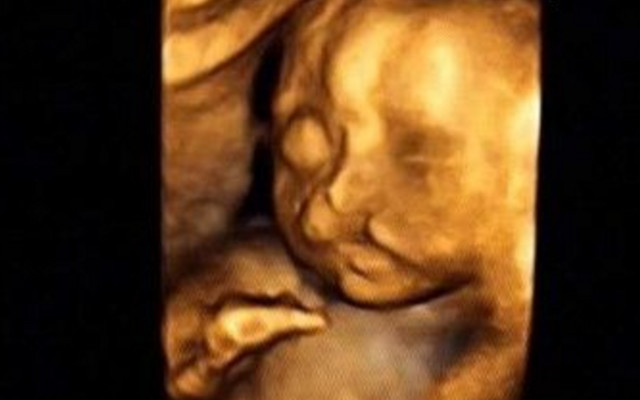

30岁的小孙就有唇裂,修补过的疤痕仍很分明。在最近一次三维B超显示,腹中的胎儿居然中度唇裂。她通知大夫,因为她诞生就有唇裂,小时老是被讪笑和厌弃。所有,无论怎样也要流掉腹中的宝宝,她不想让她的孩子再经历这样的经历。

大夫却通知小孙,现在已经孕21周,如果引产对身材损伤十分大,如果在次怀孕,不能包证就不会得唇腭裂,第二次仍会怀上唇腭裂宝宝的几率约为4%,假如怀过两次唇腭裂的宝宝,第三次怀上唇腭裂宝宝的几率会提升到14%。如今婴儿唇腭裂整形手艺,已经十分胜利,即使是重度的唇腭裂,仍是能够修补得简直看不出来了。倡议把孩子生上去,不要因为这点瑕疵,就将宝宝的性命闭幕。